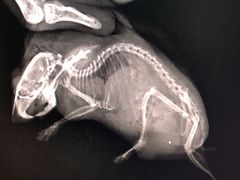

• 爱侣宠医·鹦鹉专科·小型哺乳类·异宠专科(灵石路店)

• -爱侣宠医·鹦鹉专科·小型哺乳类·异宠专科(灵石路店)

沉雪轻盈 | 20-10-25